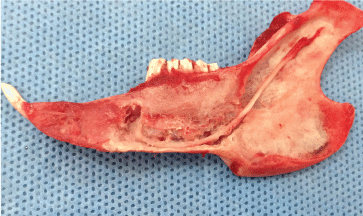

Anatomical measurements for the inferior alveolar nerve

After exiting the skull, the inferior alveolar nerve travels along the medial mandibular ascending branch and the gap between muscles, downwards into the mandibular foramen (Figure 3), and then along the mandibular nerve canal, with branches emitted at various roots and the mandible. The mental nerve was observed on the outer surface of the stripped soft tissue and piercing from the mental foramen (Figure 4). The inferior alveolar nerve in the mandibular body is located approximately 1 mm above the lower edge of the mandible and below the molar root tip, traveling outwards from the mesial site of the first molar to pierce the mental foramen into the periosteum and subcutaneous soft tissues (Figure 5).

Figure 5: The path and distribution of the inferior alveolar nerve in the mandible (medial view). View Figure 5